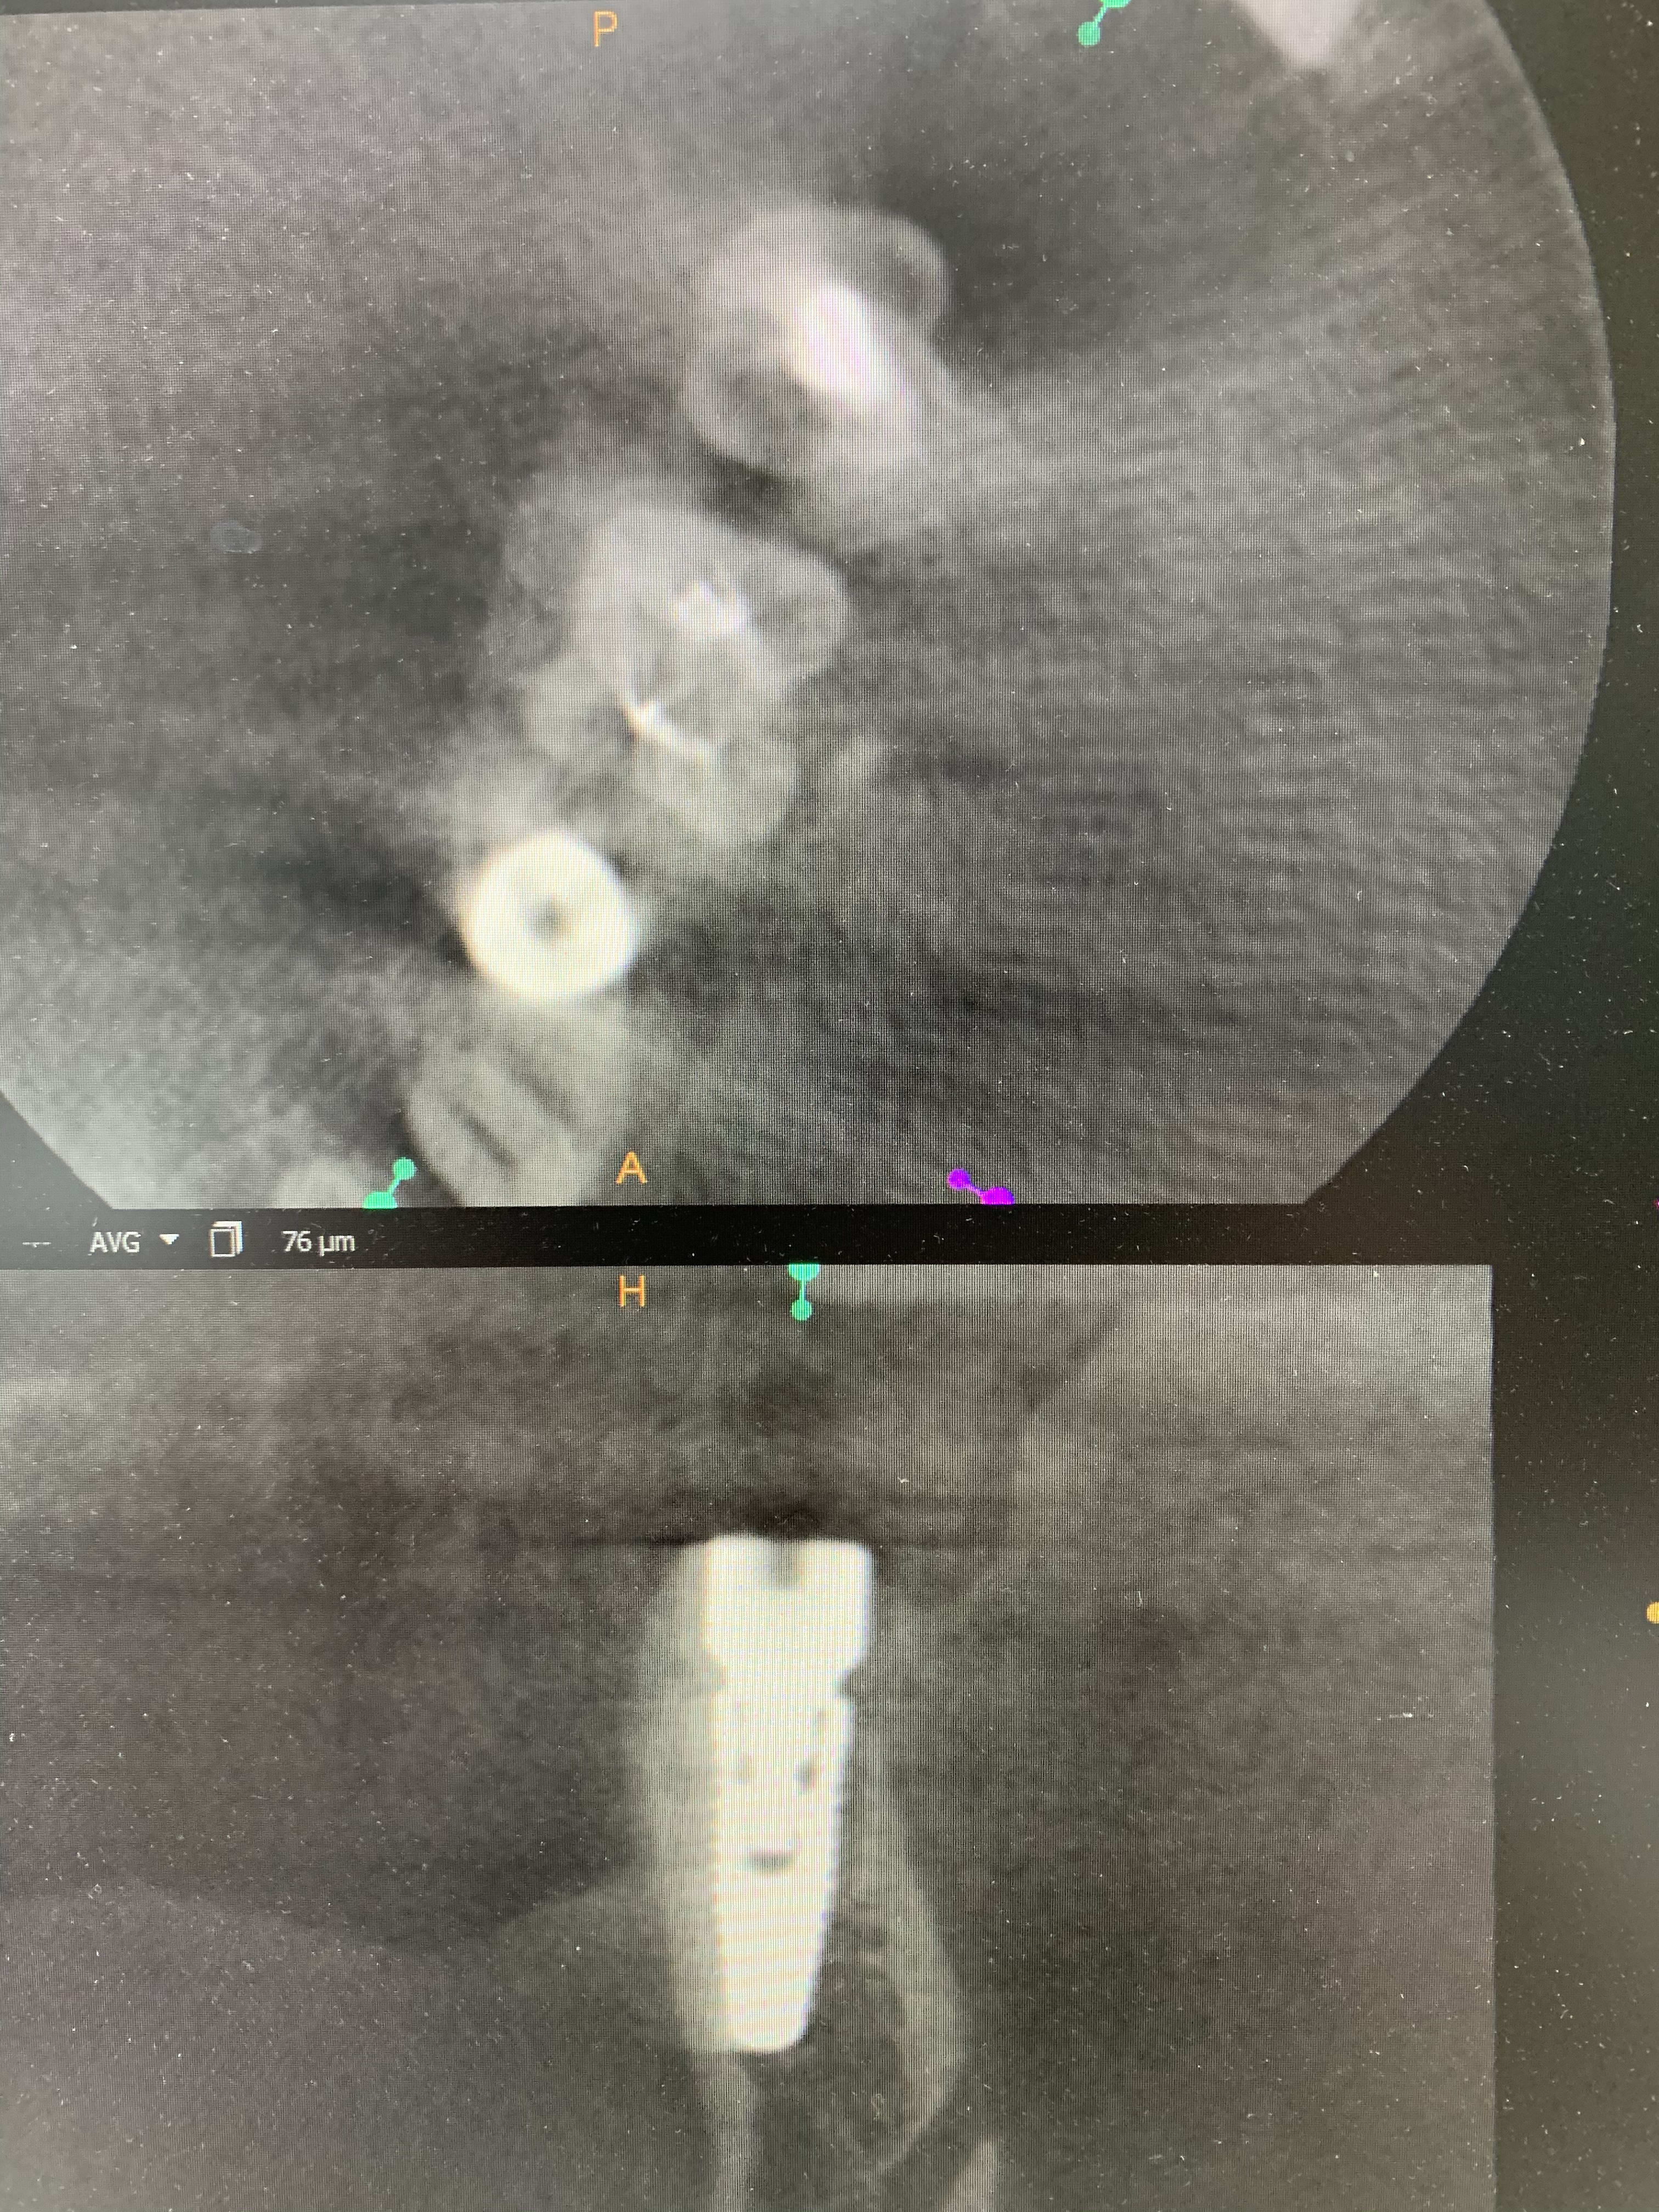

Les artefacts métalliques sont bien différents selon les machines.

A l’adf on me dit « regardez on voit même les spires des implants », avec ma bécanne de 2008 je vois les spires des vis dans les implants, les têtes de vis... je n’ai rien vu d’équivalent sur les machines récentes.

Regardez comme les tenons sont bien trop larges à la radio !

Les implants sont de gros pâtés blancs...